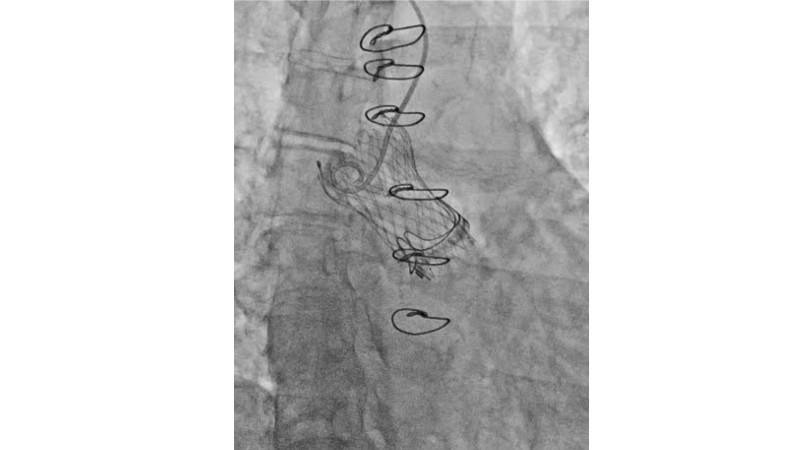

This session explores the evolving landscape of transcatheter aortic valve implantation (TAVI) with a focus on supra-annular valve technology. It covers techniques for achieving commissural alignment, considerations for small aortic annuli, and advantages in treating bicuspid aortic valve disease, supported by clinical data and illustrative cases.

- To learn how to perform TAVI resulting in commissural alignment and easier coronary access